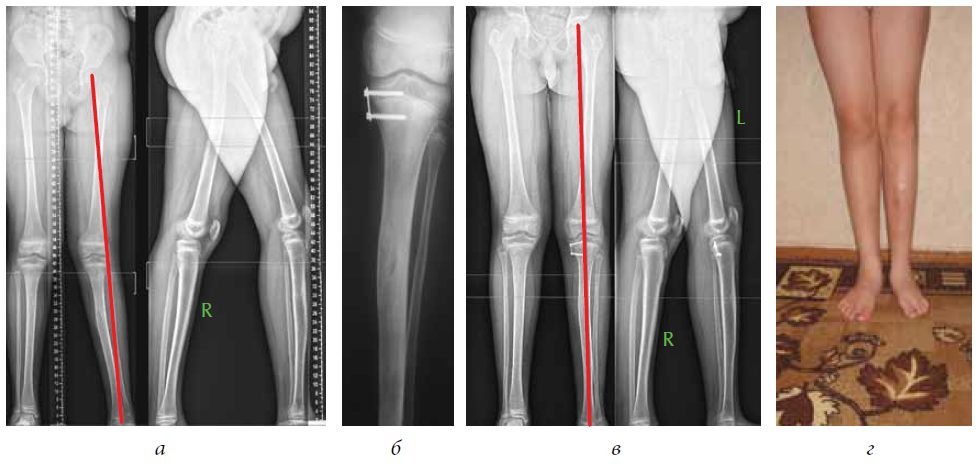

Здоровье на первом месте: диагностика и лечение через рентгеноскопию конечностей

Раздел: Снимки-откровения